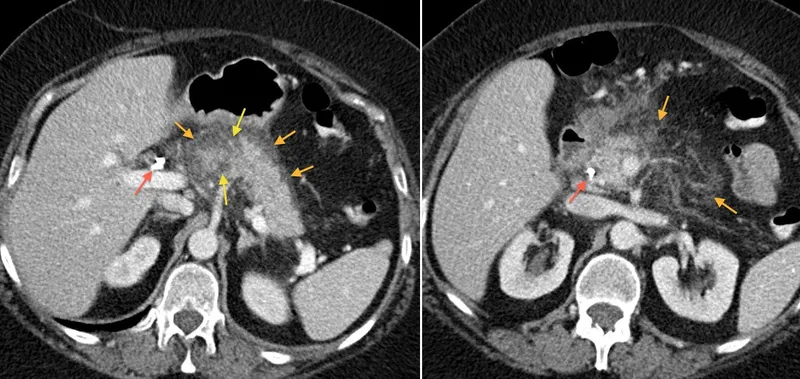

Managing follows a treat-to-target strategy, with mucosal healing as the therapeutic endpoint reducing long-term complications by 50%. NICE NG129 recommends starting moderate-to-severe Crohn's with corticosteroids (prednisolone 40 mg daily, taper over 8 weeks) plus azathioprine 2-2.5 mg/kg for maintenance. Failure to achieve remission by 12 weeks mandates biologics: infliximab 5 mg/kg at weeks 0, 2, 6, then 8-weekly. For , endoscopic haemostasis (adrenaline injection plus thermal coagulation) achieves initial control in 90% of cases, but rebleeding occurs in 10-20%-requiring repeat endoscopy or interventional radiology.